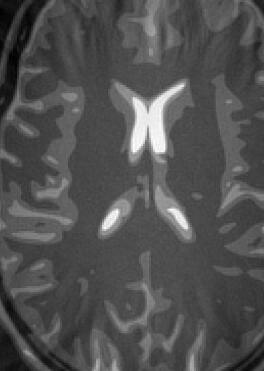

Fig. 14 exhibits the reconstruction results with the spiral trajectory with for . The reconstructed images are displayed alongside profile plots of row . The same is also presented in Figures 13 for .

When sampling on a spiral trajectory, SPURS further demonstrates its superior performance over the other methods. For values high enough, SPURS, NUFFT and rBURS with achieve very good results, but the performance curve for each method levels off for different values of (Figures 9, 10, 11 and 12). Iterative SPURS levels off for values as low as , requiring about iterations to converge to its best result. For these low values, significant artifacts appear in the reconstructed image produced by all methods excluding SPURS as presented in Fig. 13 for and Fig. 14 for . The performance curve of the NUFFT method and of a single iteration of SPURS level off at around . For and higher, a single iteration of SPURS produces marginally better results than those produced by NUFFT, which requires about iterations to converge. Among the other non-iterative methods, both rBURS with and convolutional gridding perform similarly well for , however the results are still inferior to those of a single iteration of SPURS, all of which have similar computational complexity.